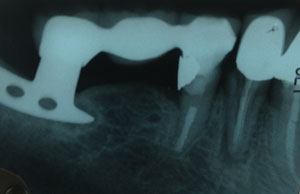

Image shows a root canal treated tooth anchoring one side of a bridge, an implant anchoring the other side